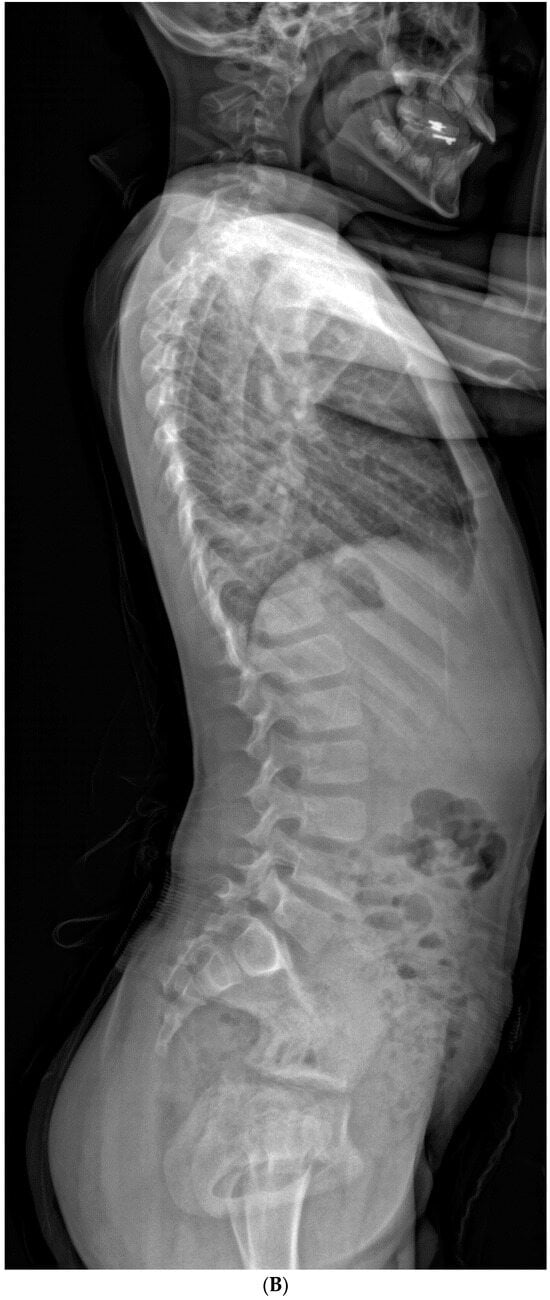

Patients in the “progression” cohort presented with a significantly larger T1S compared to the “no progression” cohort (32.4° ± 14.0° vs. 23.8 ± 7.1°, respectively; p = 0.041, effect size = 0.78). Individual patients with T1S ≥ 25° were found to be 4.62 times more likely to undergo progression than those who did not (Figure 5A–D and Figure 6A–D). Although these findings mostly trended toward significance, patients in the “progression” cohort also had lower C2-SVA (20.8° ± 30.7° vs. 57.5° ± 41.1°, p = 0.053), small thoracic curves (33.2° ± 20.6° vs. 54.1° ± 22.6°, p = 0.063), greater LL (59.3° ± 13.2° vs. 45.3° ± 12.1°, p = 0.056), and smaller interval change in C2-CSVL (−4.9° ± 21.8° vs. 18.4° ± 23.1°, p = 0.069).

Figure 6.

(A,B) Initial PA and lateral radiograph of a 2-year-old child presenting with 17° of scoliosis at the cervicothoracic junction and T1 slope of 11°. (C,D) Follow-up radiographs showing a stable curve approximating 18° 4 years later.